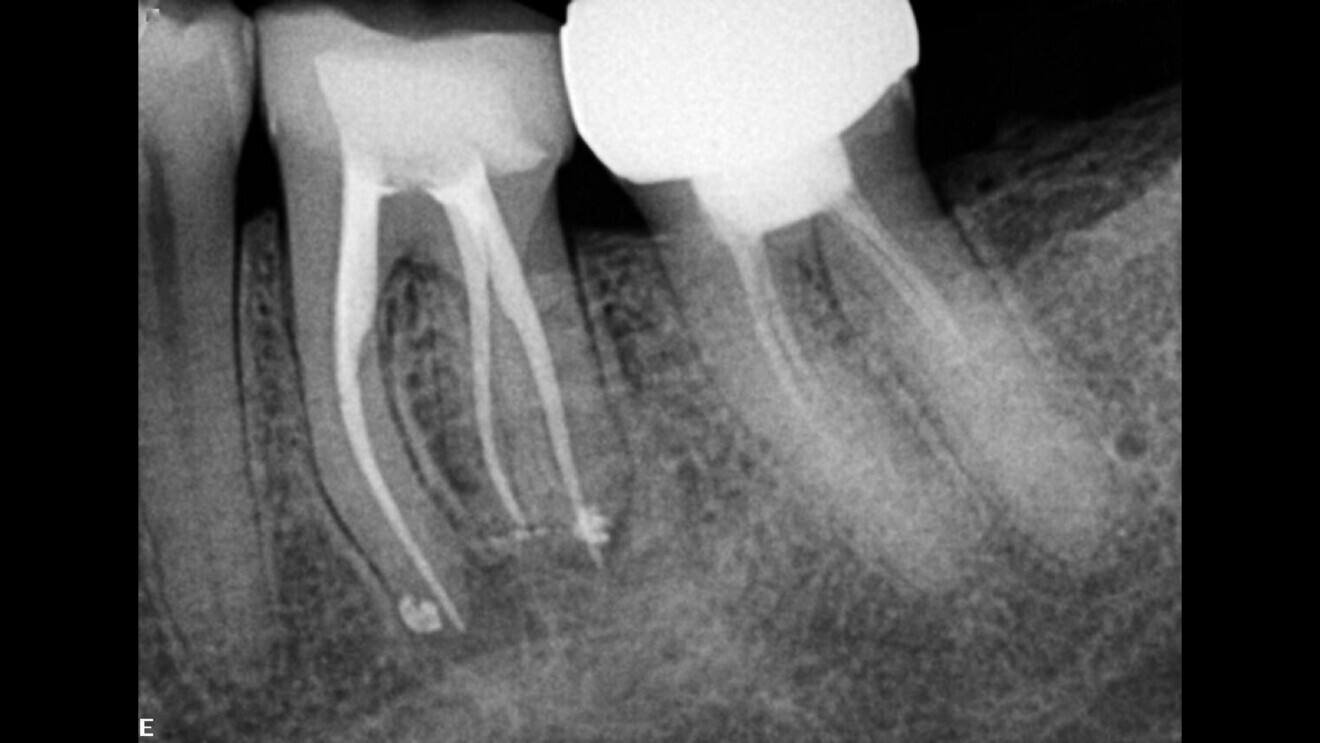

Irrigation in endodontics is widely misunderstood, yet it is so simple when we understand the chemicals that we are using and what our goal is and how to achieve it. By giving each chemical the work or the target that it is supposed to achieve and by understanding chemical interactions—irrigation is a matter of dealing with different kinds of chemicals—we can achieve better, much faster and safer root canal disinfection. Before the use of sodium hypochlorite, it took up to 20–30 minutes, and now it takes seconds. A bacterial level of zero is in our reach, and it does not take rocket science to achieve it. Zero bacteria means that we can have a better prognosis for the root canal treatment and higher success rates for our retreatment as well in a single visit and no temporary dressing needed—the myth of calcium hydroxide is no more. By way of demonstration, consider the case of a necrotic molar with a relatively large radiolucency that we treated with a root canal treatment in a single visit following our irrigation protocol (Figs. 4–6).

Fig. 4: Necrotic molar with a relatively large radiolucency.